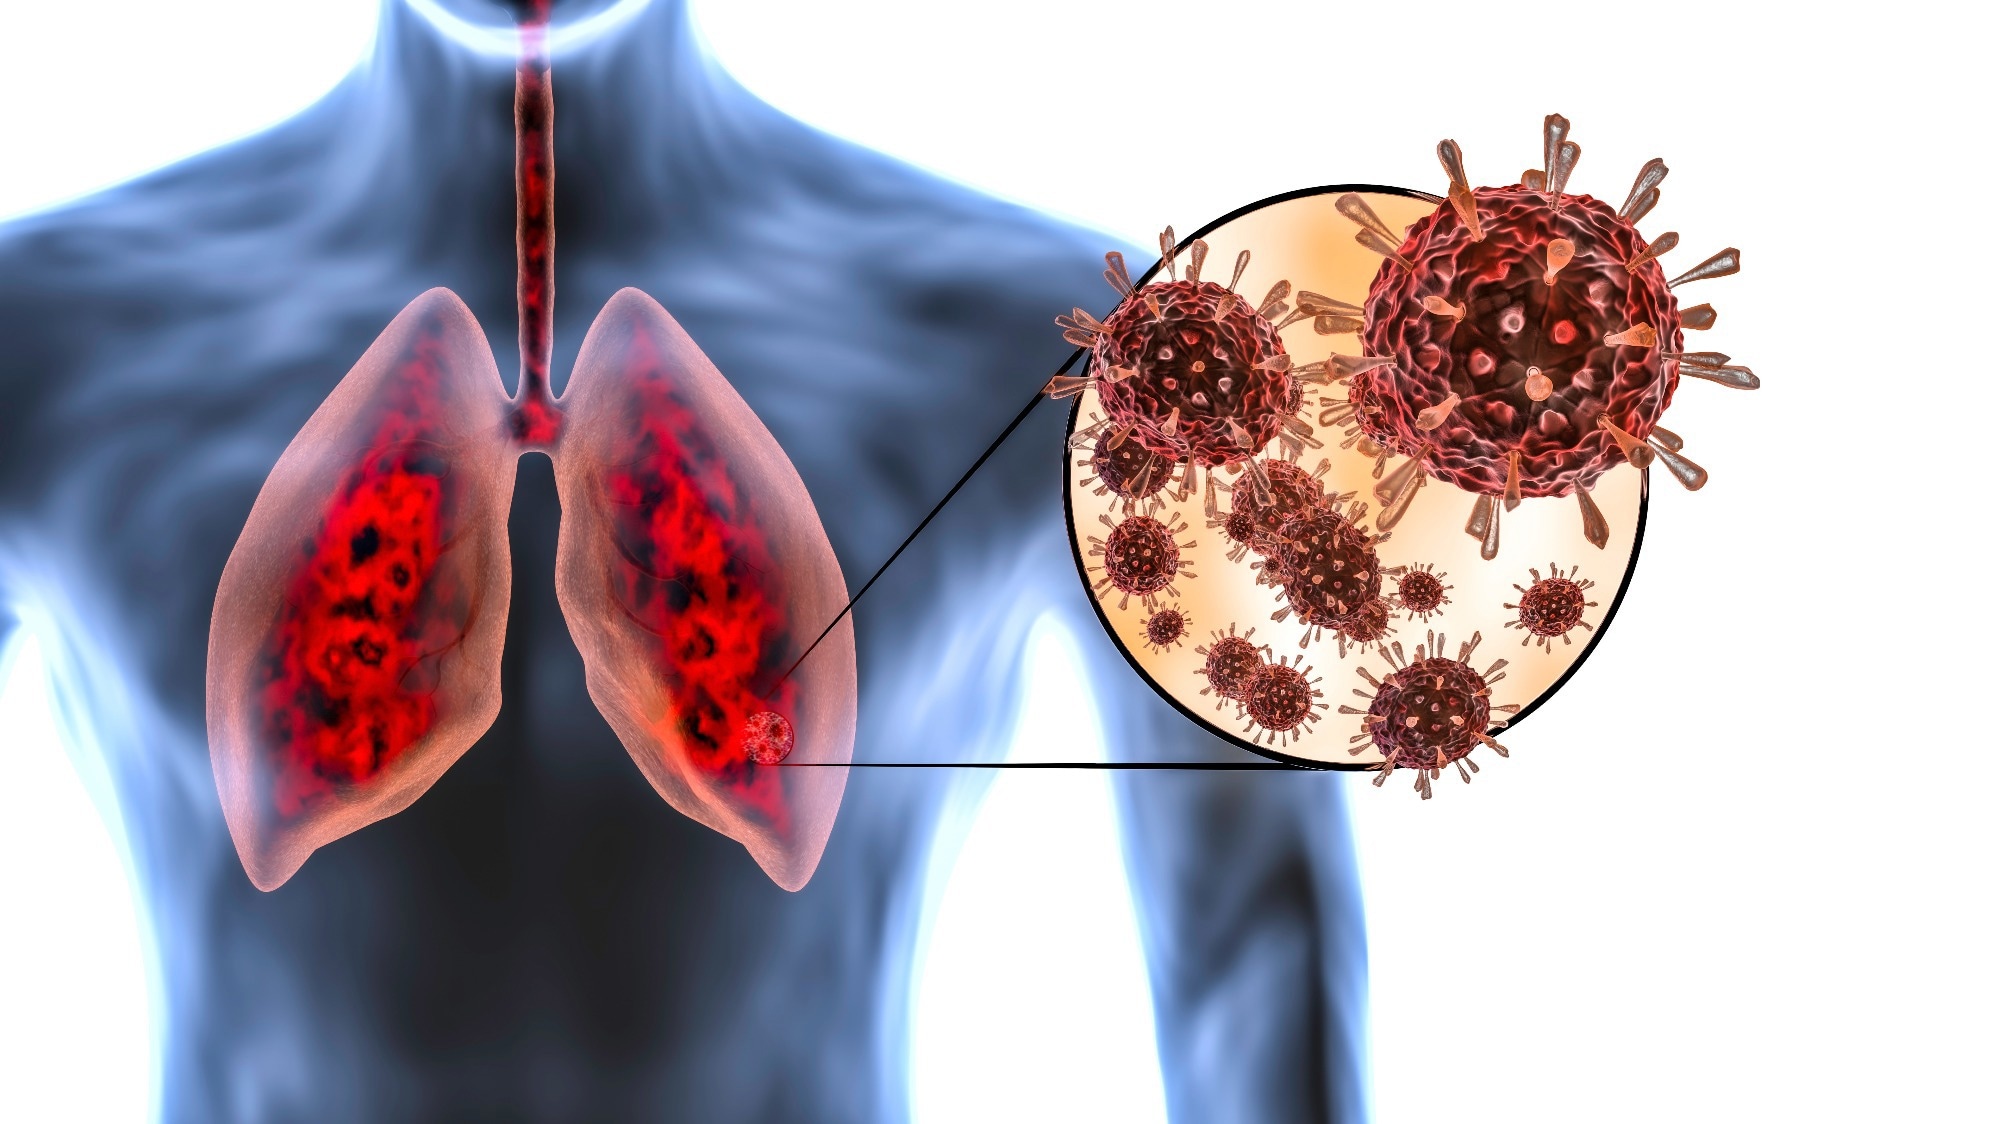

Пневмония - это серьезное заболевание легких, которое может быть вызвано различными причинами, включая бактериальные, вирусные и грибковые инфекции. Для того чтобы наглядно показать симптомы, диагностику и лечение этого заболевания, картинки могут быть очень полезны.

Поражение легких при коронавирусе

Легкие зараженный Ковидом